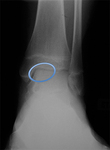

Preoperative radiograph with large osteochondritis lesion of the femoral condyle

From the collection of H. Chambers, MD